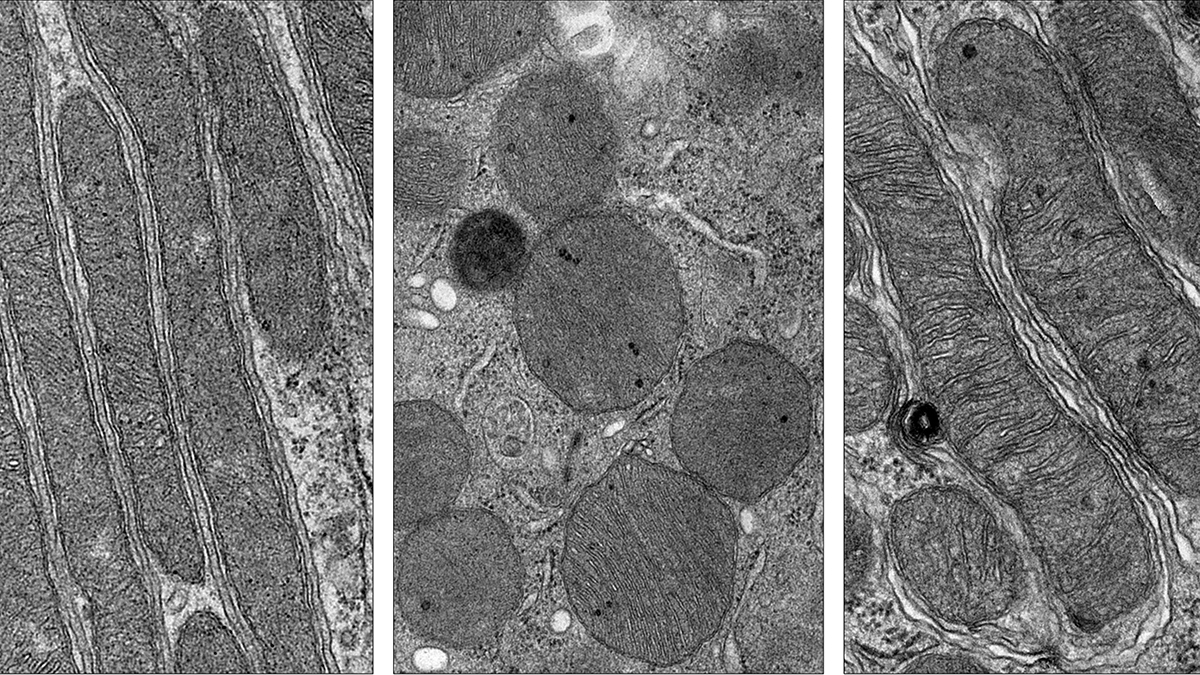

The recent studies, published in News-Medical and Genetic Engineering and Biotechnology News, pinpoint ceramides – a class of lipid molecules – as key instigators of mitochondrial dysfunction during AKI. When the kidneys are injured, ceramide levels surge, directly damaging mitochondria and crippling their ability to produce energy. This energy deficit then cascades into cellular dysfunction and ultimately, organ failure. The newly developed drug effectively targets and neutralizes these harmful ceramides, protecting the mitochondria and preserving kidney function in mouse models.

Mitochondria are often called the “powerhouses of the cell,” and for good reason. They generate the adenosine triphosphate (ATP) that fuels virtually every cellular process. But their role extends far beyond energy production. They also regulate cell death, calcium signaling, and immune responses. A healthy mitochondrial network is crucial for maintaining cellular homeostasis and resilience, particularly in organs like the kidneys that are constantly exposed to toxins and stress.